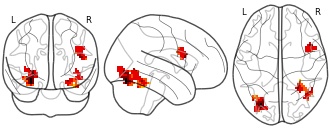

"name": "Multi_VBMgreater_fMRIenhanced",

"description": "Multi-modal analysis in BPD. Brain regions exhibiting greater gray matter and enhanced activation during emotion processing in BPD compared to healthy controls. Note: Results were thresholded at p<.0025. Note2: Results were updated (see Erratum for this publication).",

"name": "Multi_VBMsmaller_fMRIenhanced",

"description": "Multi-modal analysis in BPD. Brain regions exhibiting smaller gray matter and enhanced activation during emotion processing in BPD compared to healthy controls. Note: Results were thresholded at p<.0025. Note2: Results were updated (see Erratum for this publication).",